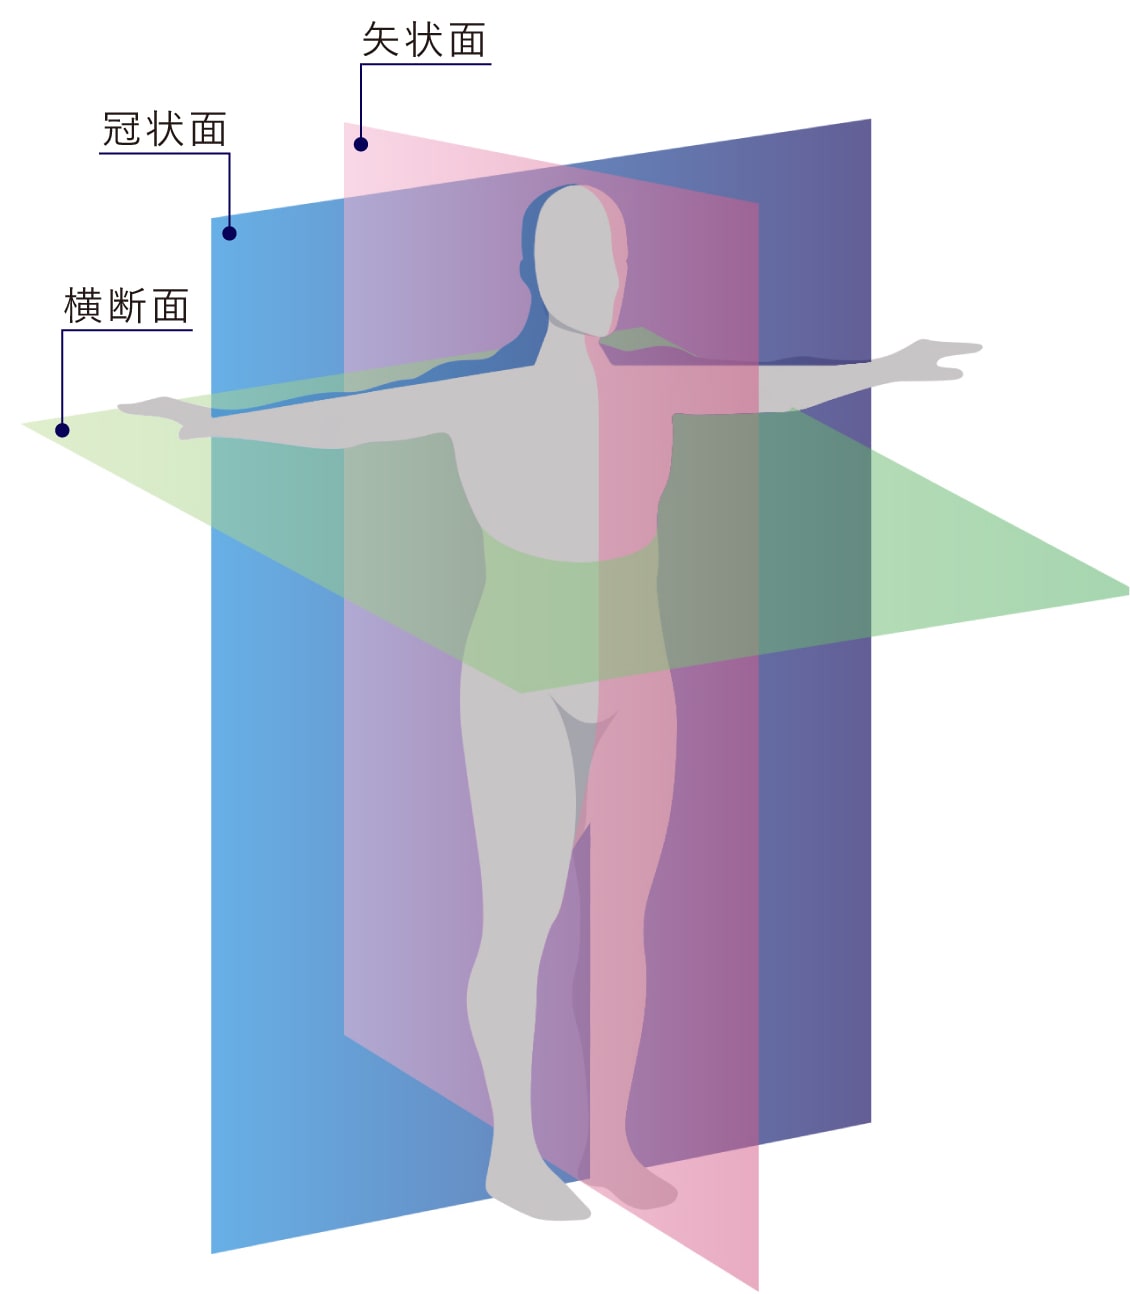

矢状面、冠状面、水平面が分からない? これで完全理解!! 身体の方向をあらわす3つの基準面 矢状面、冠状面、水平面 、本当に理解している?ここって、結構間違えやすい部分だよね。 なので、今回は「矢状面 正中面 」「冠状面」「水平面」のそれぞれの覚え方を。

身体の方向をあらわす3つの基準面 矢状面 正中面 、冠状面、水平面 のイラスト🎨 フリー素材 看護roo! カンゴルー。

矢状面、冠状面、水平面が分からない? これで完全理解!! 身体の方向をあらわす3つの基準面 矢状面、冠状面、水平面 、本当に理解している?ここって、結構間違えやすい部分だよね。 なので、今回は「矢状面 正中面 」「冠状面」「水平面」のそれぞれの覚え方を。

身体の方向をあらわす3つの基準面 矢状面 正中面 、冠状面、水平面 のイラスト🎨 フリー素材 看護roo! カンゴルー。

人体の基準面で矢状面 と 冠状面 がごっちゃになる人へ。 このイラストのイメージがあると記憶に残ります。

矢状面、冠状面、水平面が分からない? これで完全理解!! 身体の方向をあらわす3つの基準面 矢状面、冠状面、水平面 、本当に理解している?ここって、結構間違えやすい部分だよね。 なので、今回は「矢状面 正中面 」「冠状面」「水平面」のそれぞれの覚え方を。

矢状面、冠状面、水平面が分からない? これで完全理解!! 身体の方向をあらわす3つの基準面 矢状面、冠状面、水平面 、本当に理解している?ここって、結構間違えやすい部分だよね。 なので、今回は「矢状面 正中面 」「冠状面」「水平面」のそれぞれの覚え方を。

人体の3つの基準面 矢状面・冠状面・水平面.組織細胞ゴロー .体のしくみ医療系学生の勉強垢看護学生の勉強垢鍼灸科理学療法学科作業療法士の勉強垢解剖生理学ノート解剖学講座生理学ノート国試過去問柔整科歯科衛生学生ナース。